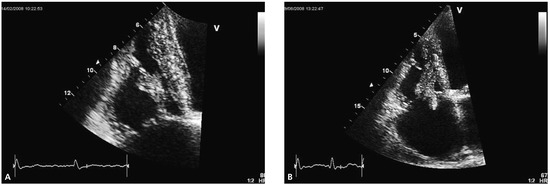

Percutaneous Implantation of an ASD Occluder with Intracardiac Ultrasound

by Frank Enseleit, Oliver Kretschmar and Thomas F. Lüscher

A 52-year-old female was admitted for further evaluation of a continuous heart murmur. Transthoracic echocardiography revealed a secundum type atrial septal defect (ASD II) with a size of 13 × 16 mm and considerable left-to-right shunt (Qp/Qs = 2), as well as elevated [...] Read more.

A 52-year-old female was admitted for further evaluation of a continuous heart murmur. Transthoracic echocardiography revealed a secundum type atrial septal defect (ASD II) with a size of 13 × 16 mm and considerable left-to-right shunt (Qp/Qs = 2), as well as elevated pulmonary artery pressure (RV/RA pressure gradient = 38 mm Hg) [...] Full article